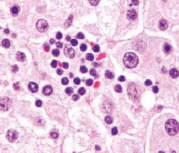

Rosai-Dorfman disease

- 大 Histiocytes 吃周圍 lymphocyte